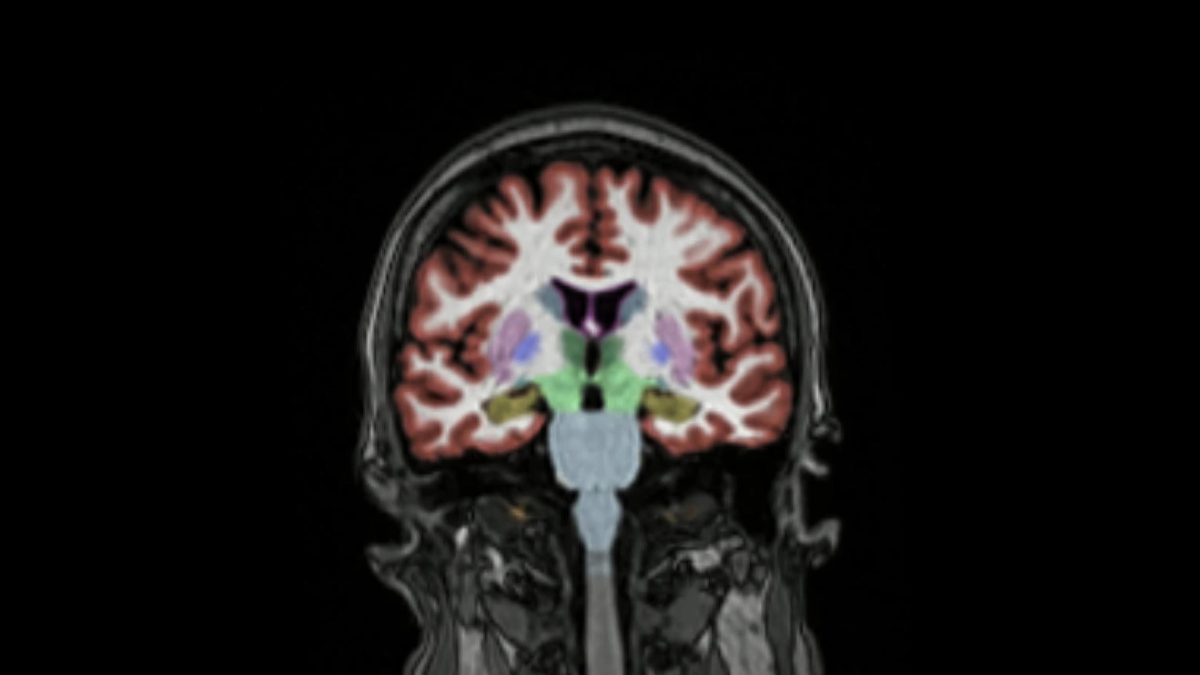

Arriva anche in Europa il primo farmaco contro l’Alzheimer

L'agenzia EMA ha finalmente approvato l'anticorpo monoclonale lecanemab. Sarà utile a chi soffre di Alzheimer in fase precoce.

L'agenzia EMA ha finalmente approvato l'anticorpo monoclonale lecanemab. Sarà utile a chi soffre di Alzheimer in fase precoce.